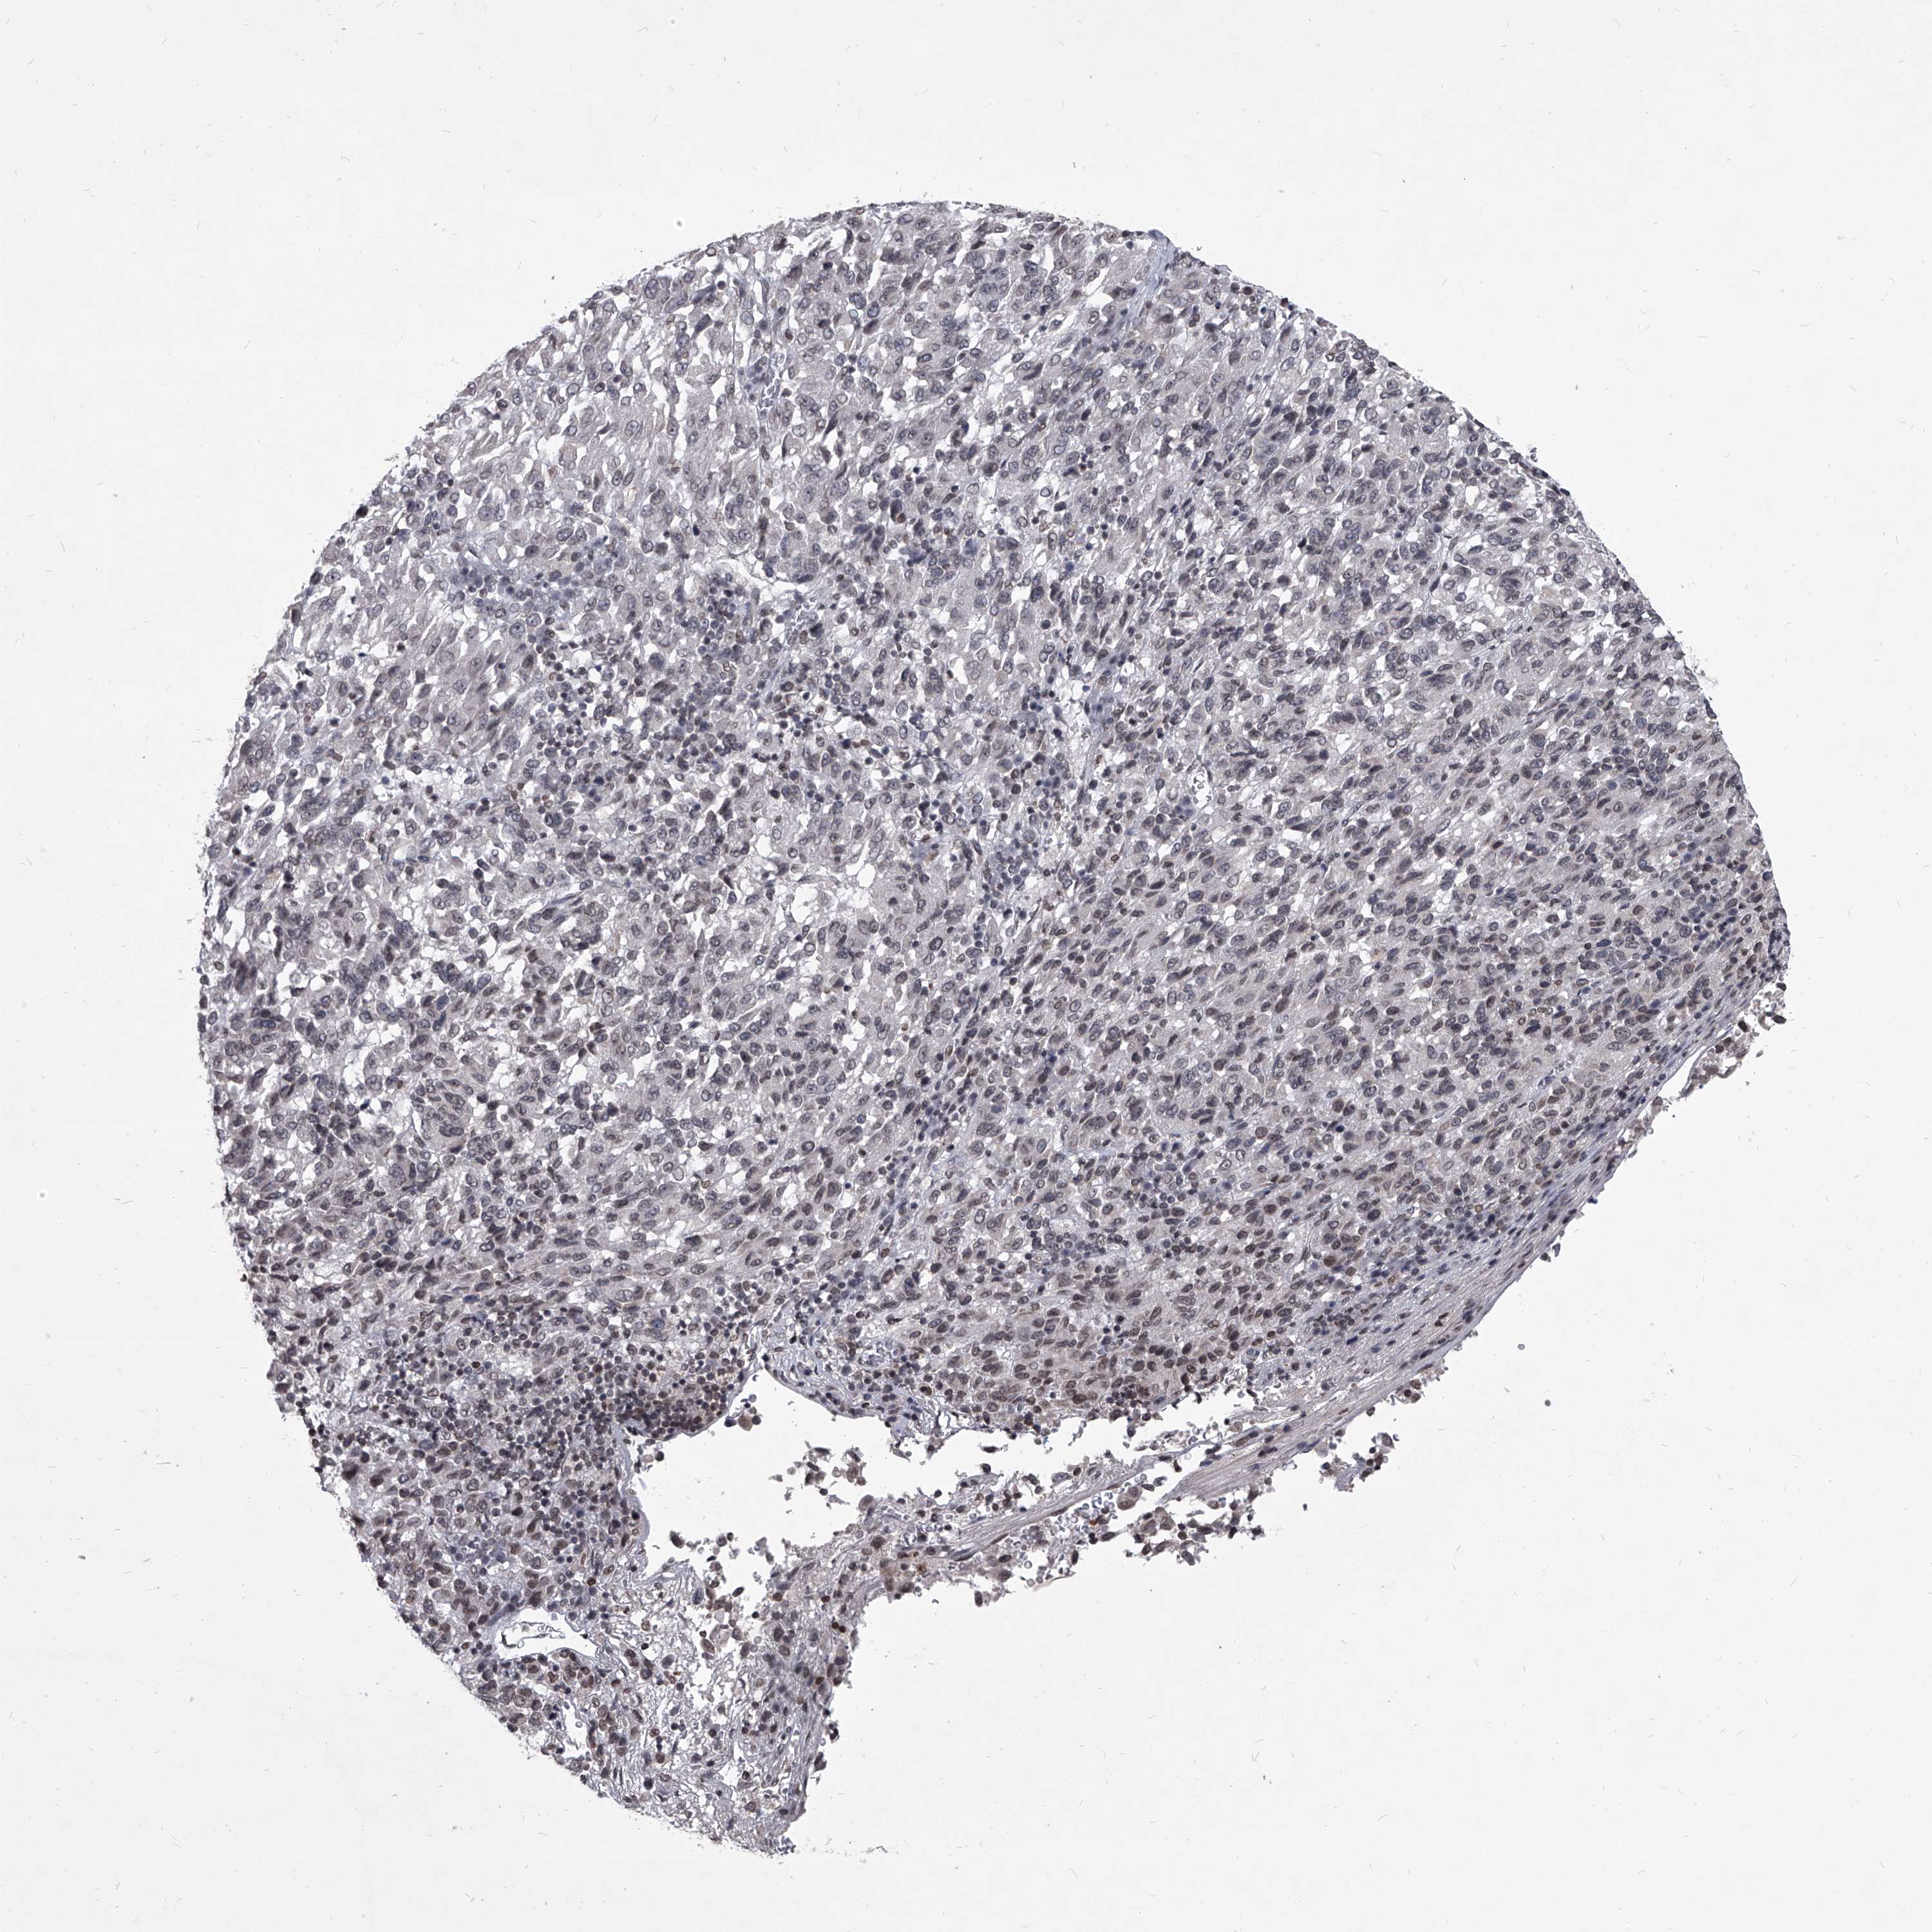

MELANOMA - Protein expressioni

A mouse-over function shows sample information and annotation data. Click on an image to view it in a full screen mode. Samples can be filtered based on level of antibody staining by selecting one or several of the following categories: high, medium, low and not detected. The assay and annotation is described here.

Note that samples used for immunohistochemistry by the Human Protein Atlas do not correspond to samples in the TCGA dataset.

Antibody stainingi

Antibody staining in the annotated cell types in the current human tissue is reported as not detected, low, medium, or high, based on conventional immunohistochemistry profiling in selected tissues. This score is based on the combination of the staining intensity and fraction of stained cells.

Each image is clickable and will lead to virtual microscopy that enables deeper exploration of all samples and also displays staining intensity scores, fraction scores and subcellular localization as well as patient and tissue information for each sample.

Antibody HPA031600

Staining

High

Medium

Low

Not detected

Intensity

Strong

Moderate

Weak

Negative

Quantity

>75%

75%-25%

<25%

None

Location

Nuclear

Cytoplasmic/membranous

Cytoplasmic/membranous,nuclear

Malignant melanoma, NOS

Malignant melanoma, Metastatic site